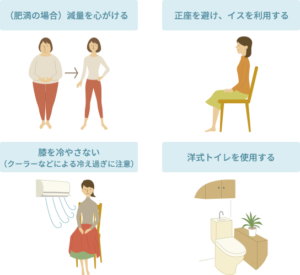

保存療法では「生活指導」を基本として、「運動療法」「薬物療法」「装具療法」を組み合わせて行います。

膝の痛みのため体を動かさず運動不足になると、膝を支える筋力が低下し、体重増加を招きます。

その結果、膝への負担が増え、痛みが増すという悪循環をきたすのでご注意下さい。